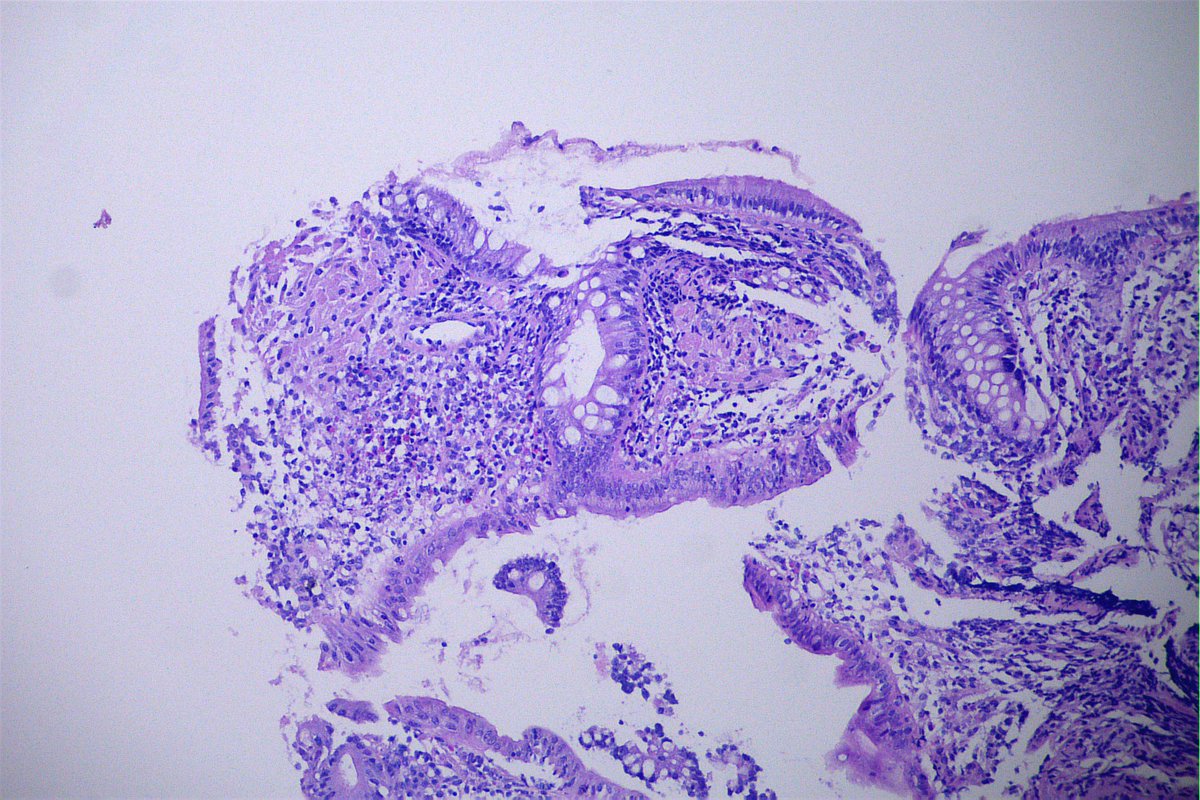

Common neighbours but infrequent bed partners...Hyperplastic polyp and tubular adenoma colliding in the same biopsy #GIPath #PathTwitter